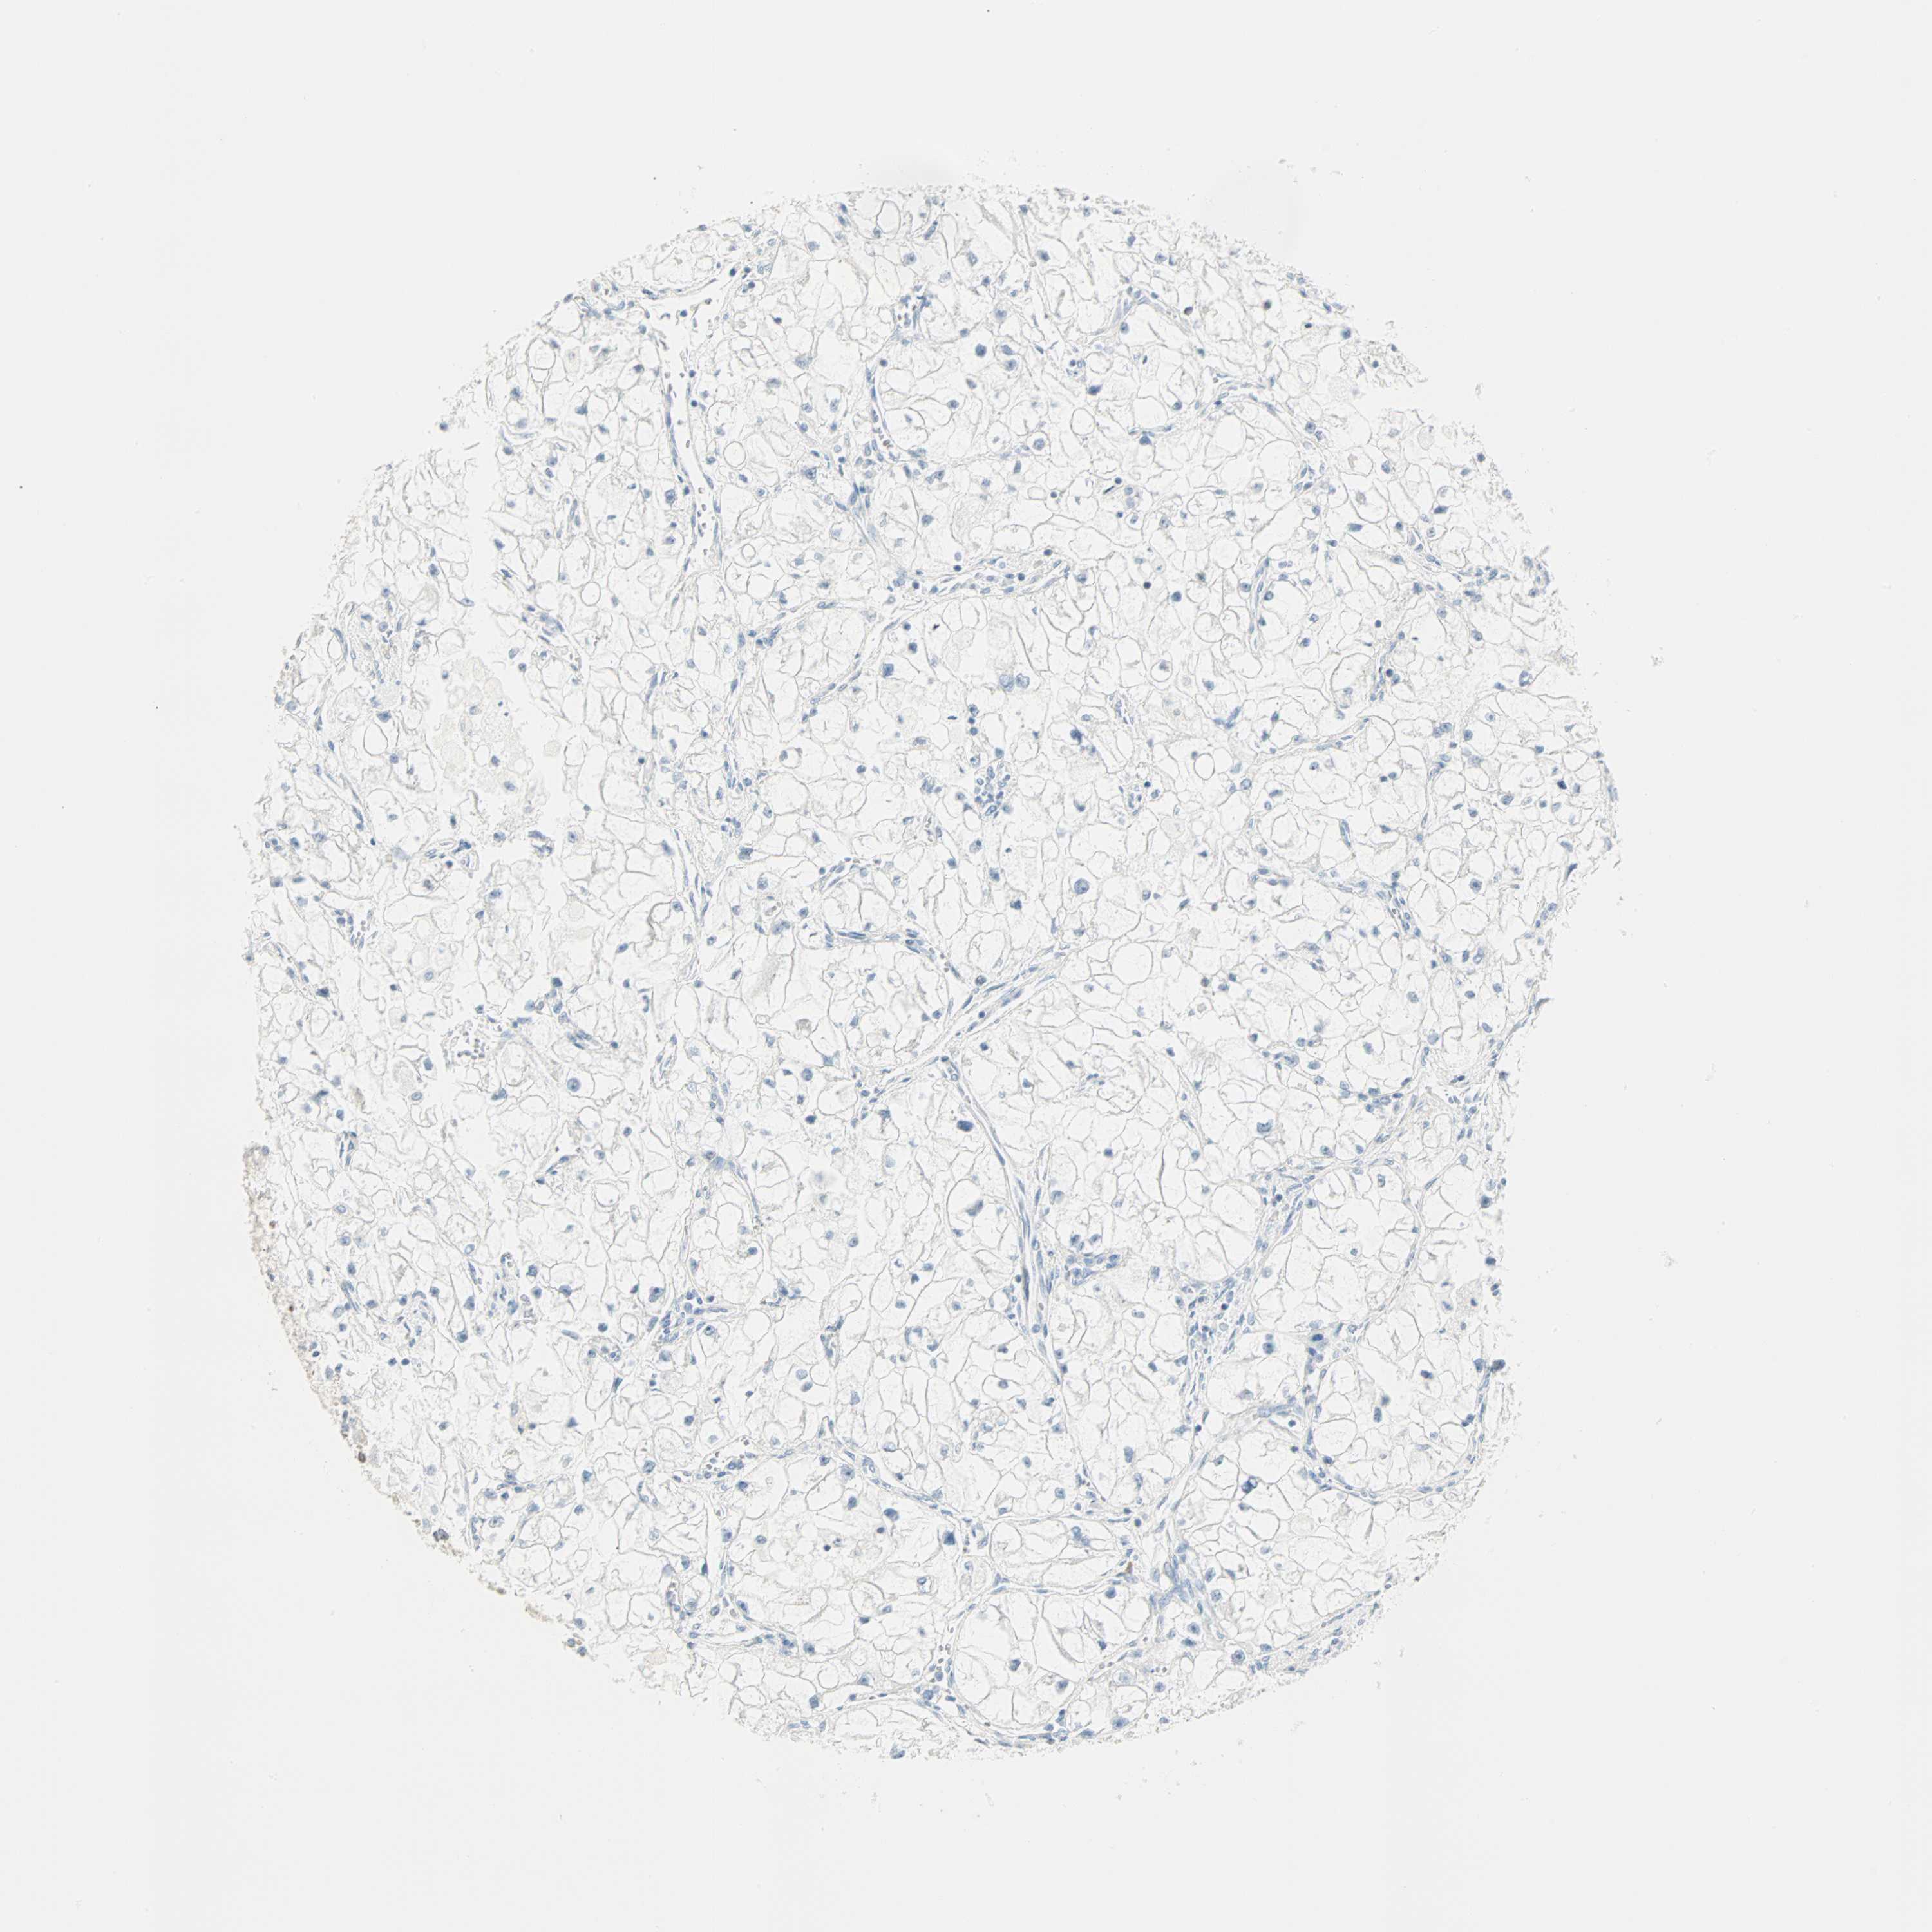

CANCER RENAL CANCER Show tissue menu

Renal cancer

Kidney chromophobe